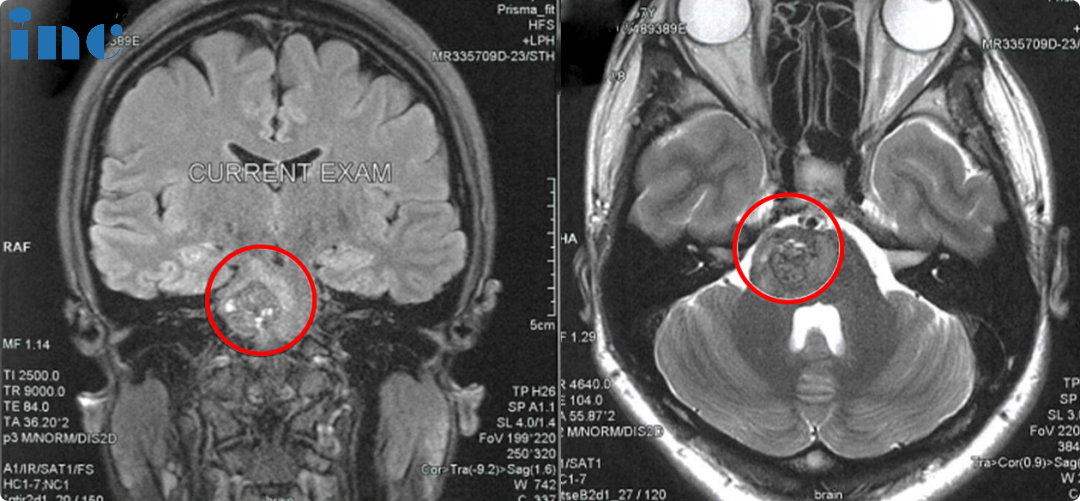

进行了术后影像复查的佩珊,也希望巴教授亲自评估影像

关于佩珊关心的复查影像,巴教授也耐心解释关于是否全切的问题

“海绵状血管瘤被切除了,所以健康的脑组织有膨胀,有点像海绵一样张开。这是正常的,海绵状血管瘤总是这样。但重要的是,它没有残瘤。”

佩珊对于影像上的一些白点表示疑问,巴教授也做出了解答

“有这些百点。这是扩张血管的一个网络,这形成了窦血管畸形,而不是海绵状血管瘤。这些血管也被挤压了,现在海绵状血管瘤被切除了,血管就变得宽一些。在磁共振影像上也可以看到。她一点不用担心这个。”